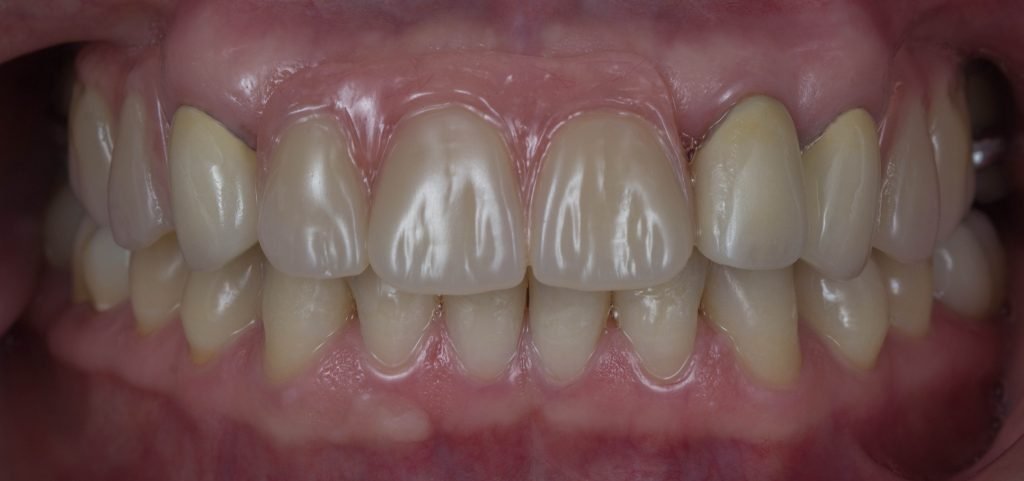

Punto Bajío Casos Clínicos Prótesis Fija sobre Implante unitario Inicio Provisional Final Prótesis Parcial Fija sobre 2 Implantes 2 Implantes Final Prótesis Bucal Removible Inicial Inicial Superior Inicial Inferior Rayos X Inicial Rayos X Inicial Frontal Final Final Superior Final Inferior Prótesis Parcial Fija/ Coronas de Circonio Sonrisa Inicial Foto Inicial Foto Inicial Inferior Foto Final Inferior Foto Final Sonrisa Final Prótesis Total Protesis Inmediatas 1 Protesis Inmediatas 2 Prótesis Removible/ Coronas Metal-Ceramica Carillas Incrustaciones Endodoncia